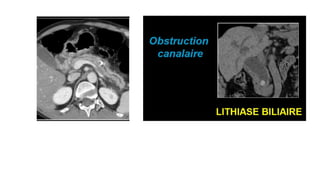

Douleur de l’HCD: Obstruction du cholédoque

TDM sans et avec injection